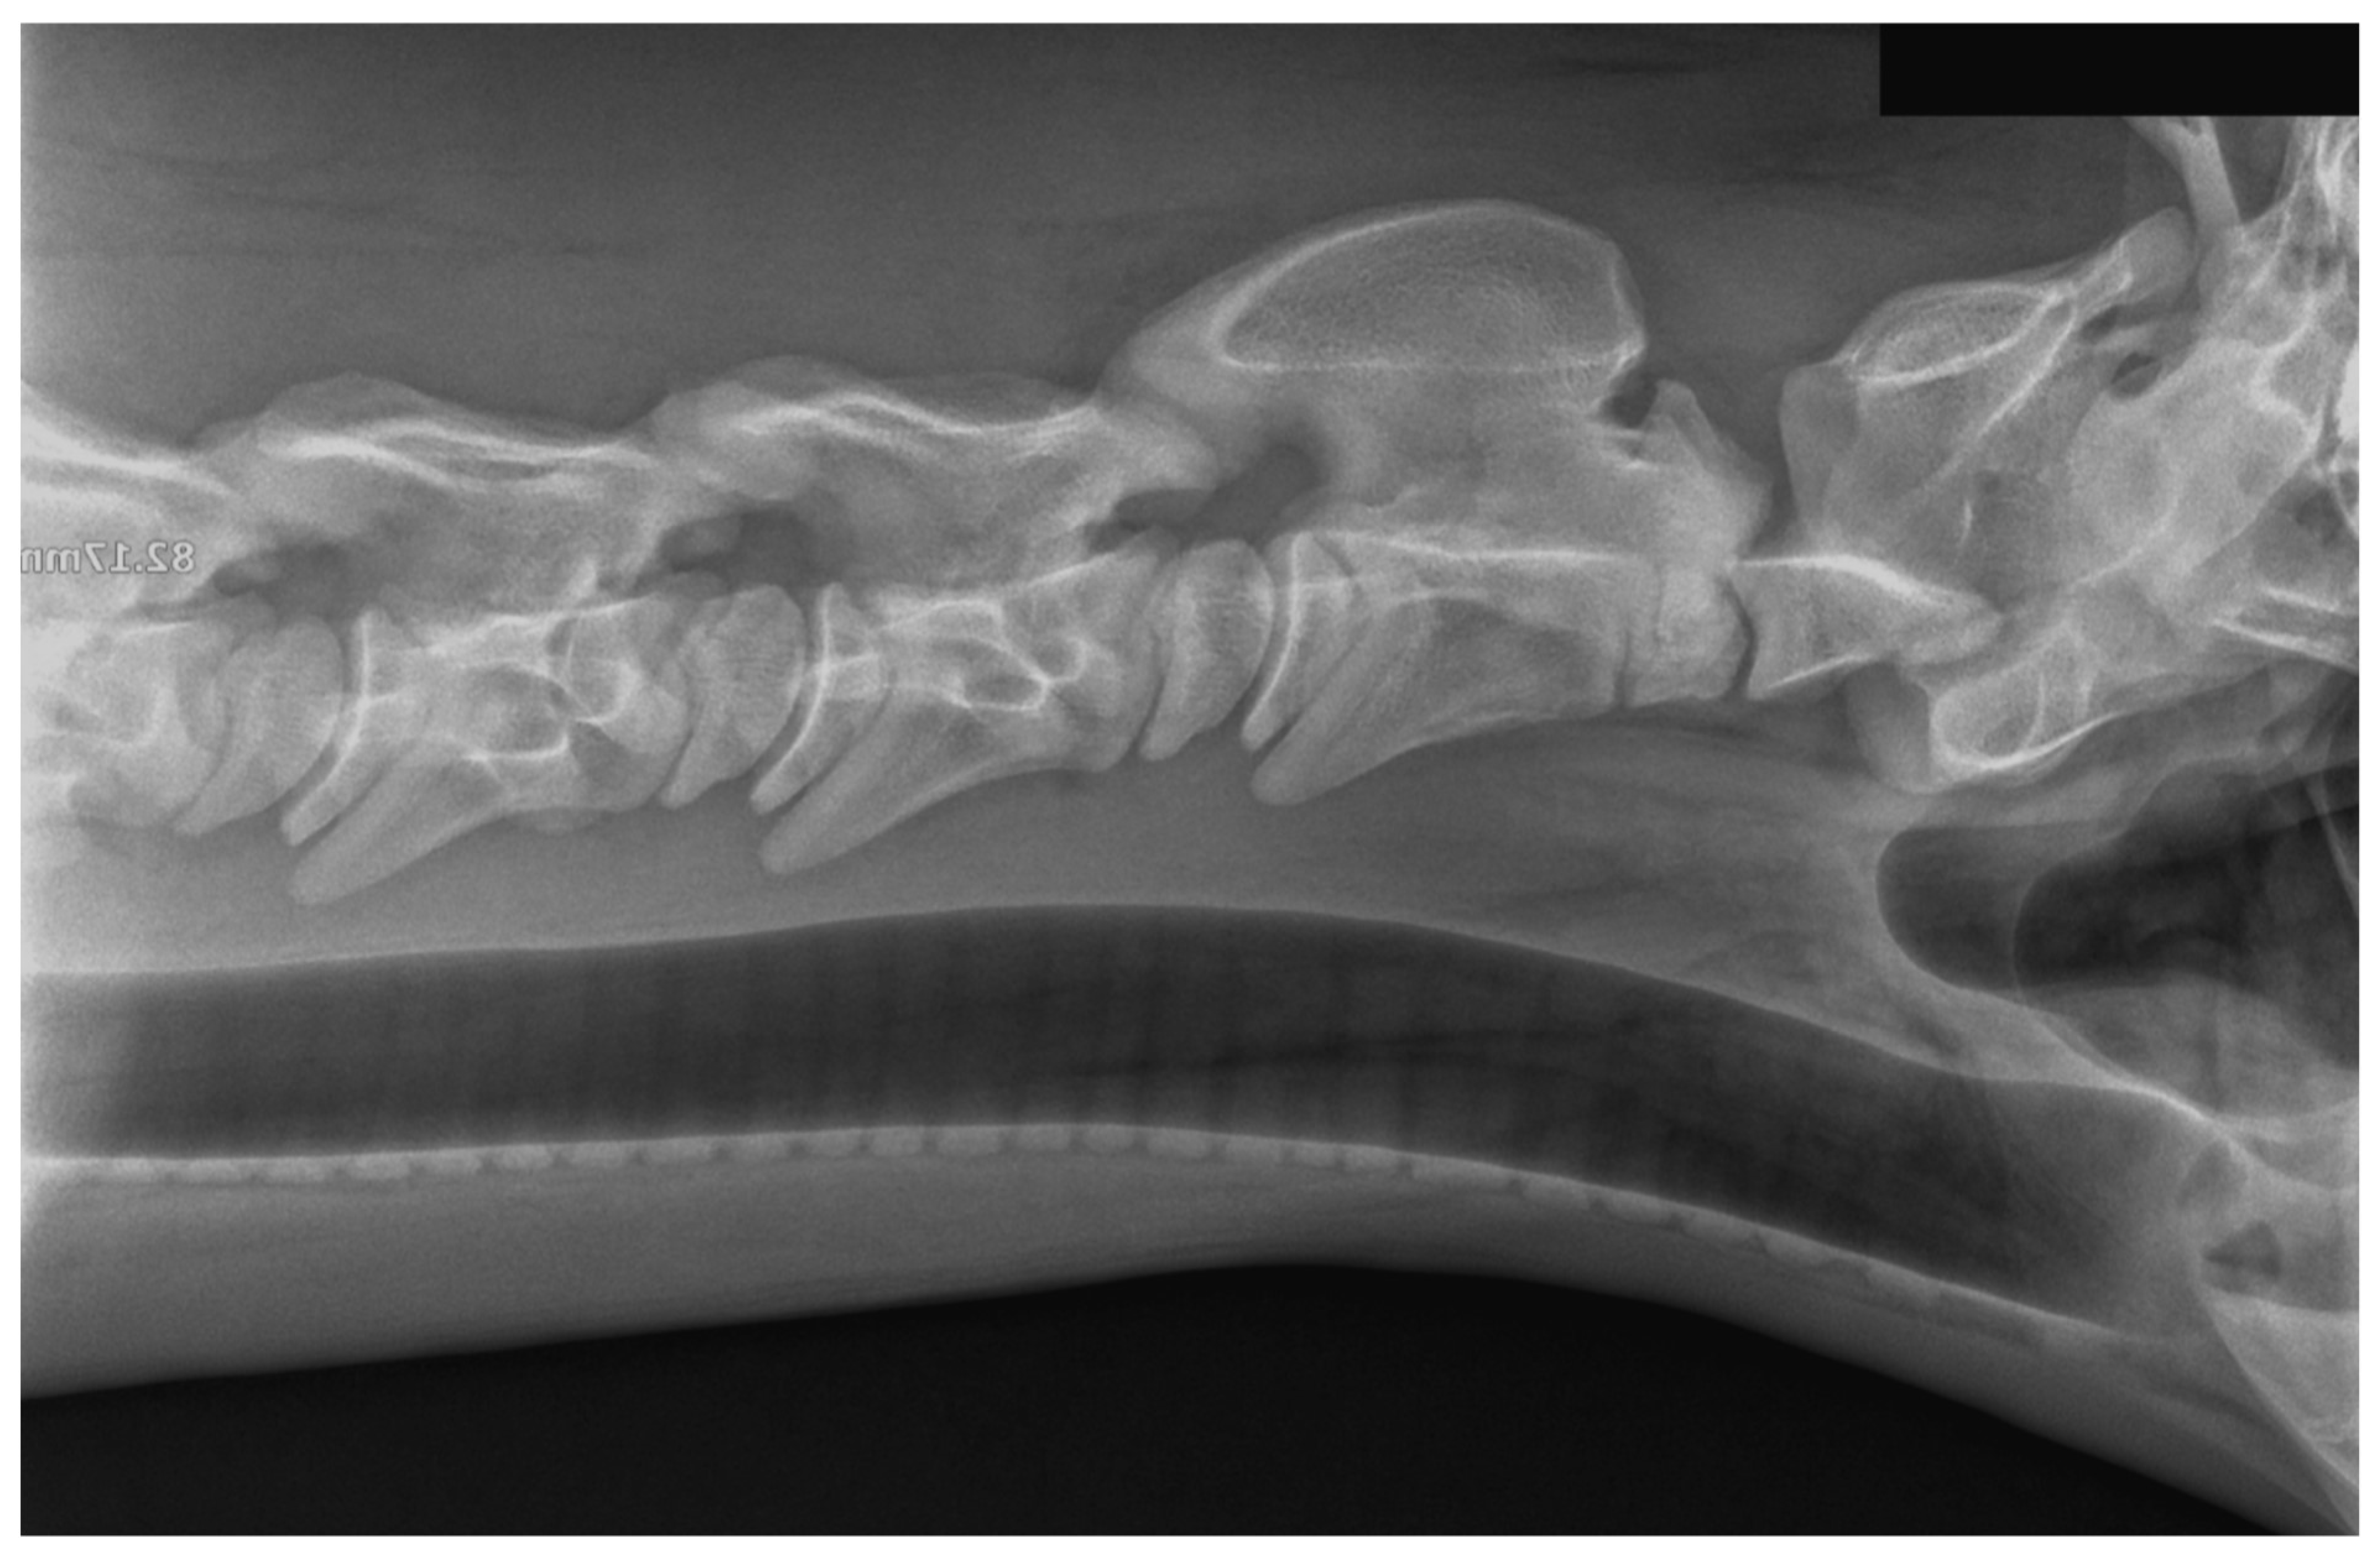

Case Presentation